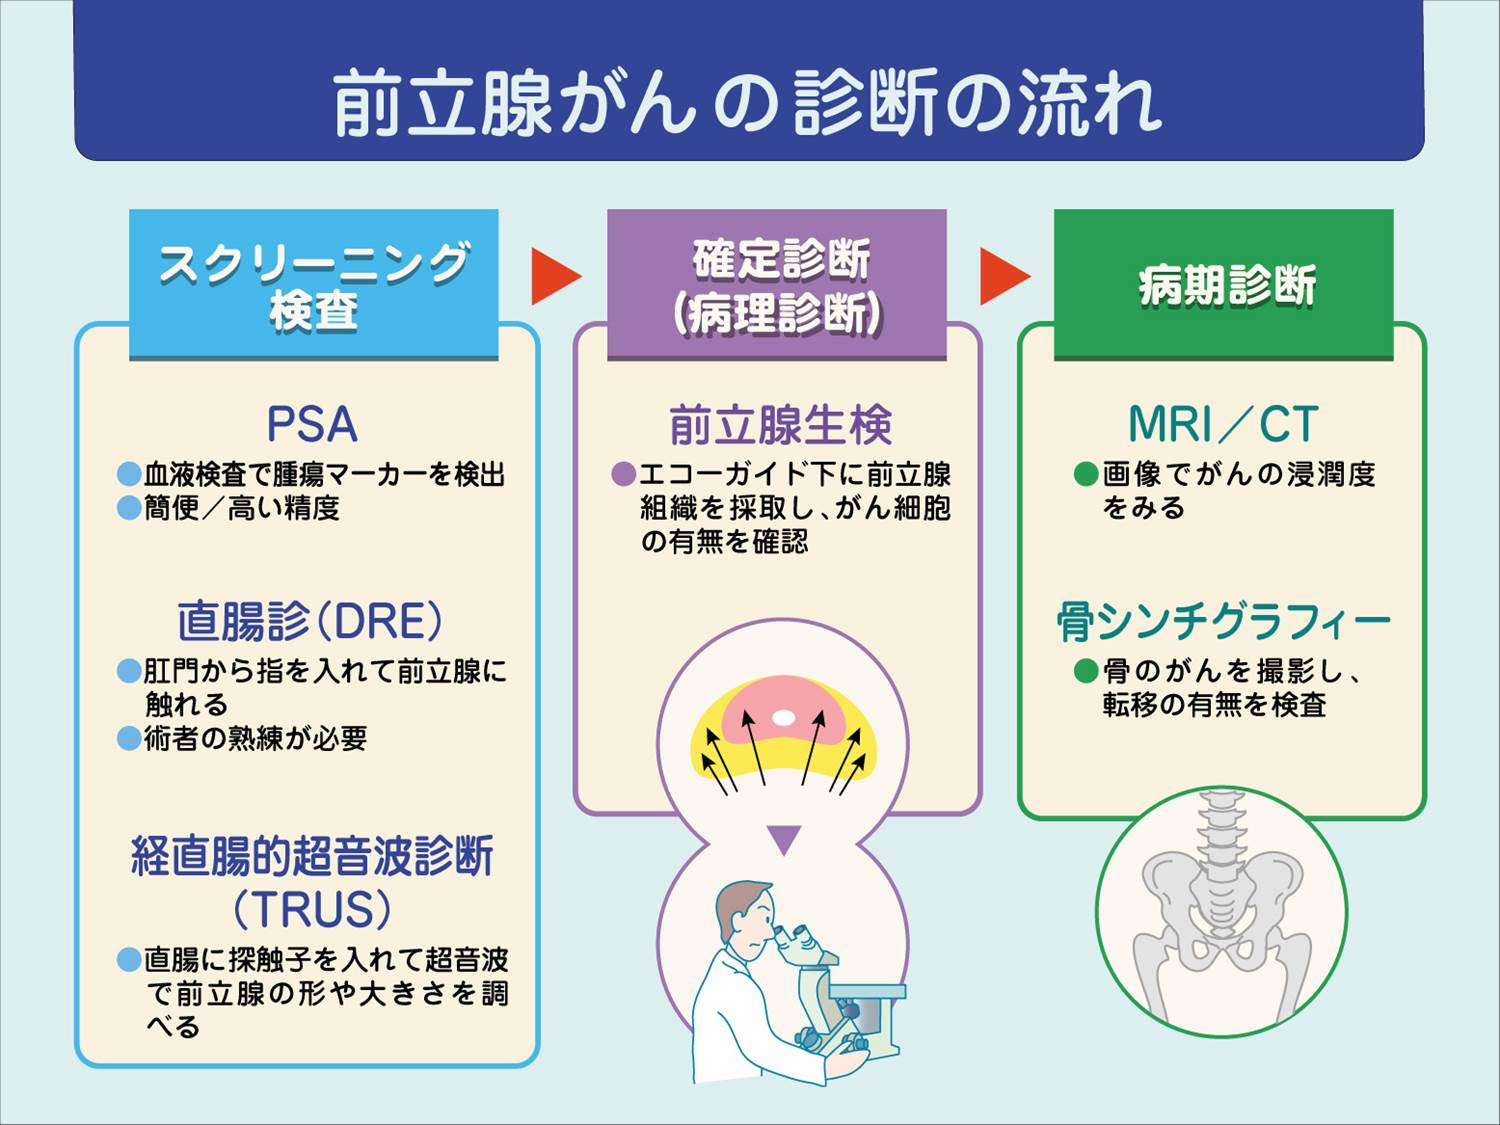

前立腺がんの検査 骨シンチグラフィー 前立腺がんの治療と名医

主な核医学検査 骨 骨シンチグラフィ 核医学検査のご案内 医療関係者

骨シンチグラフィーとは 佐賀大学病院放射線科アンオフィシャル